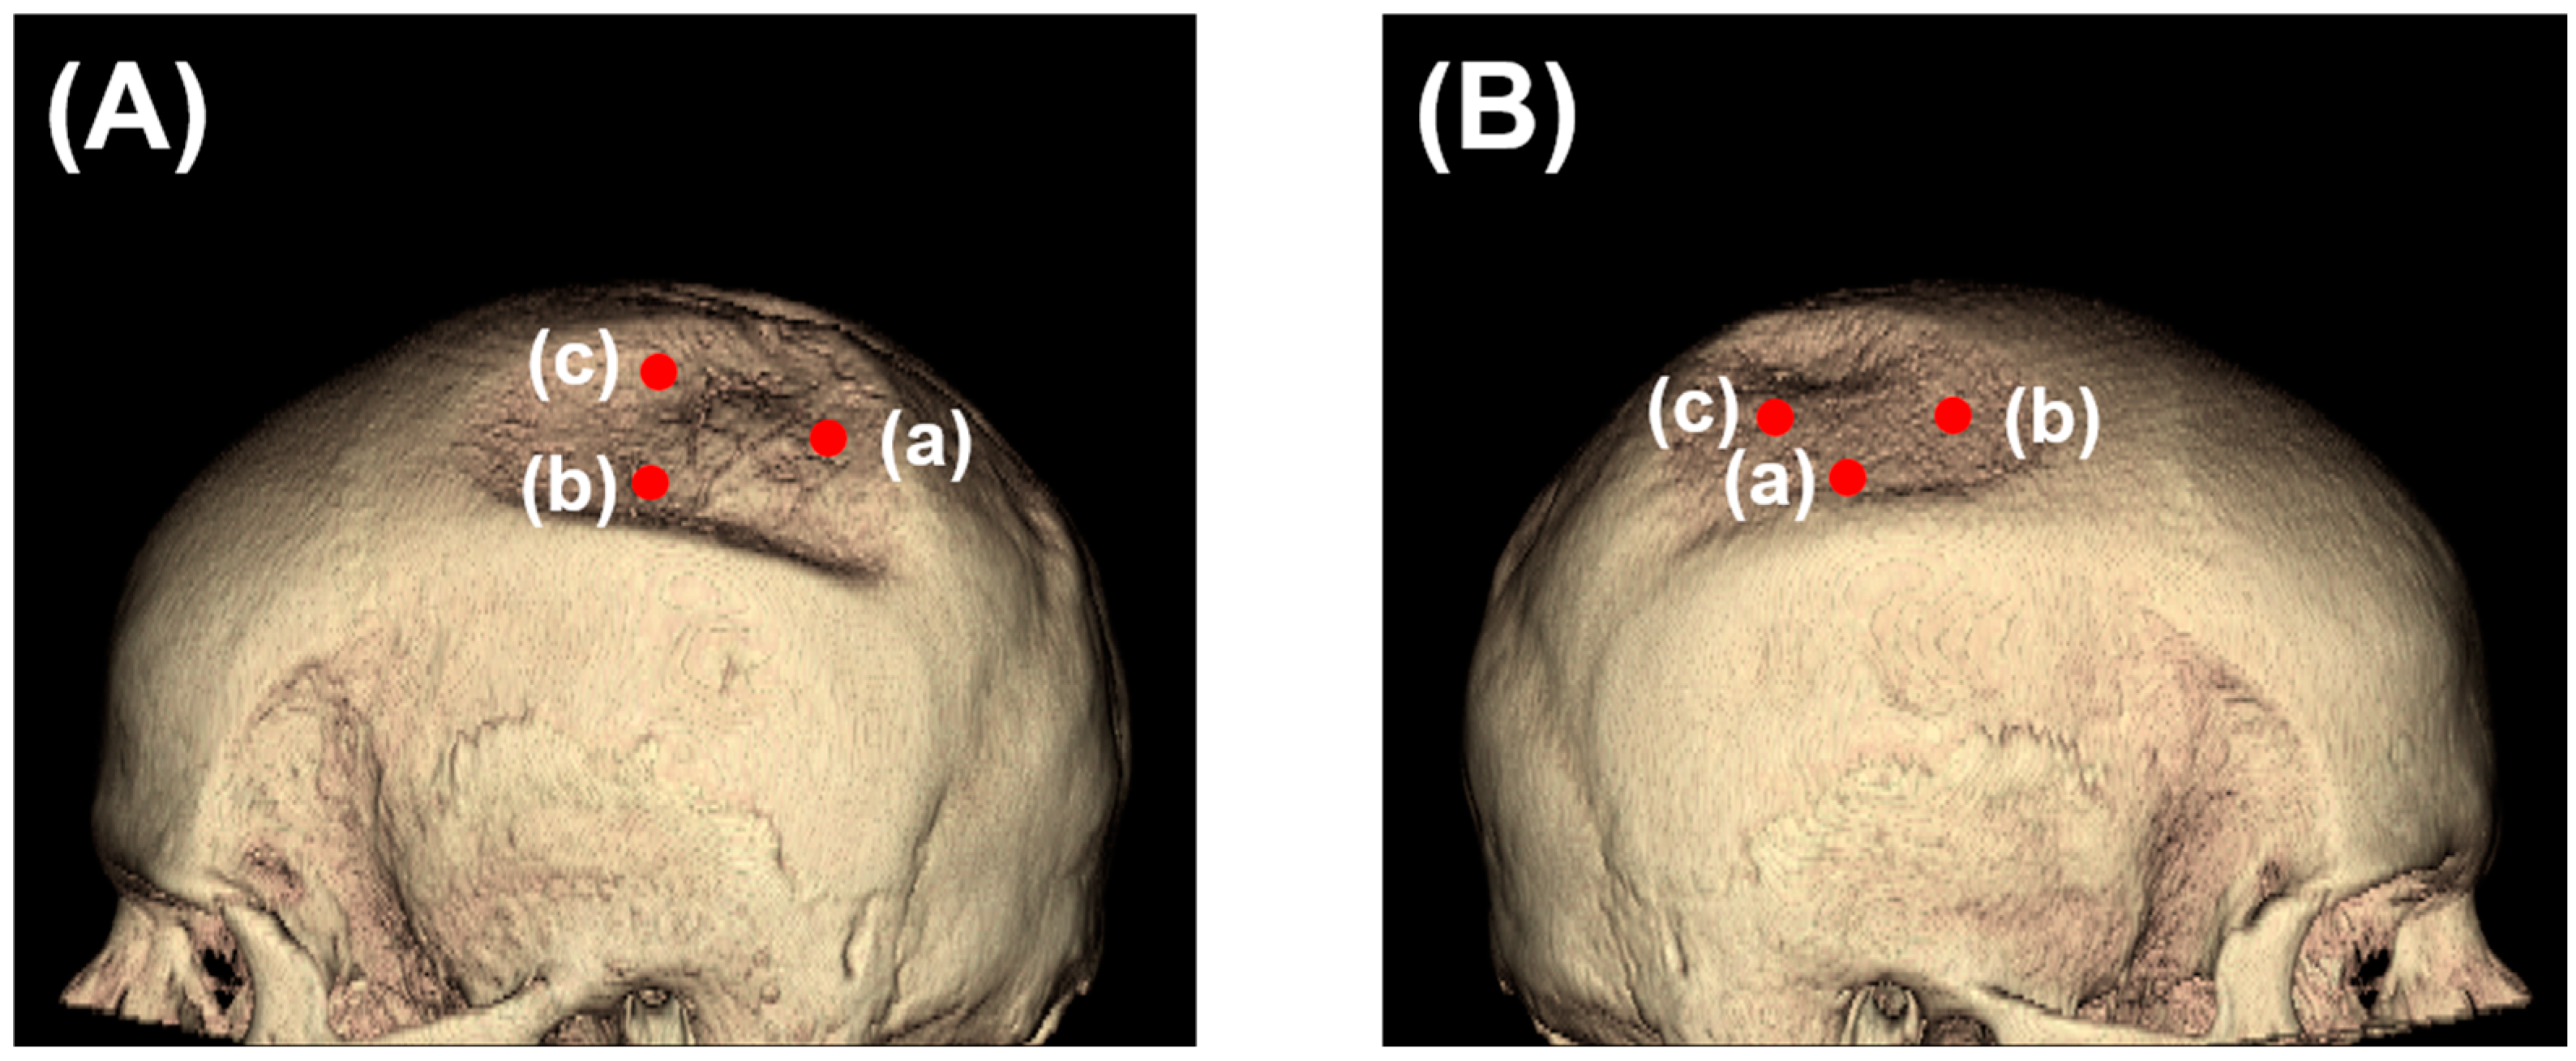

3.2. Descriptive Imaging Reports before and after 3D Reconstruction

3.3. Two-Dimensional (2D) Measurements of Biparietal Thinning

3.4. Three-Dimensional (3D) Measurements of Biparietal Thinning